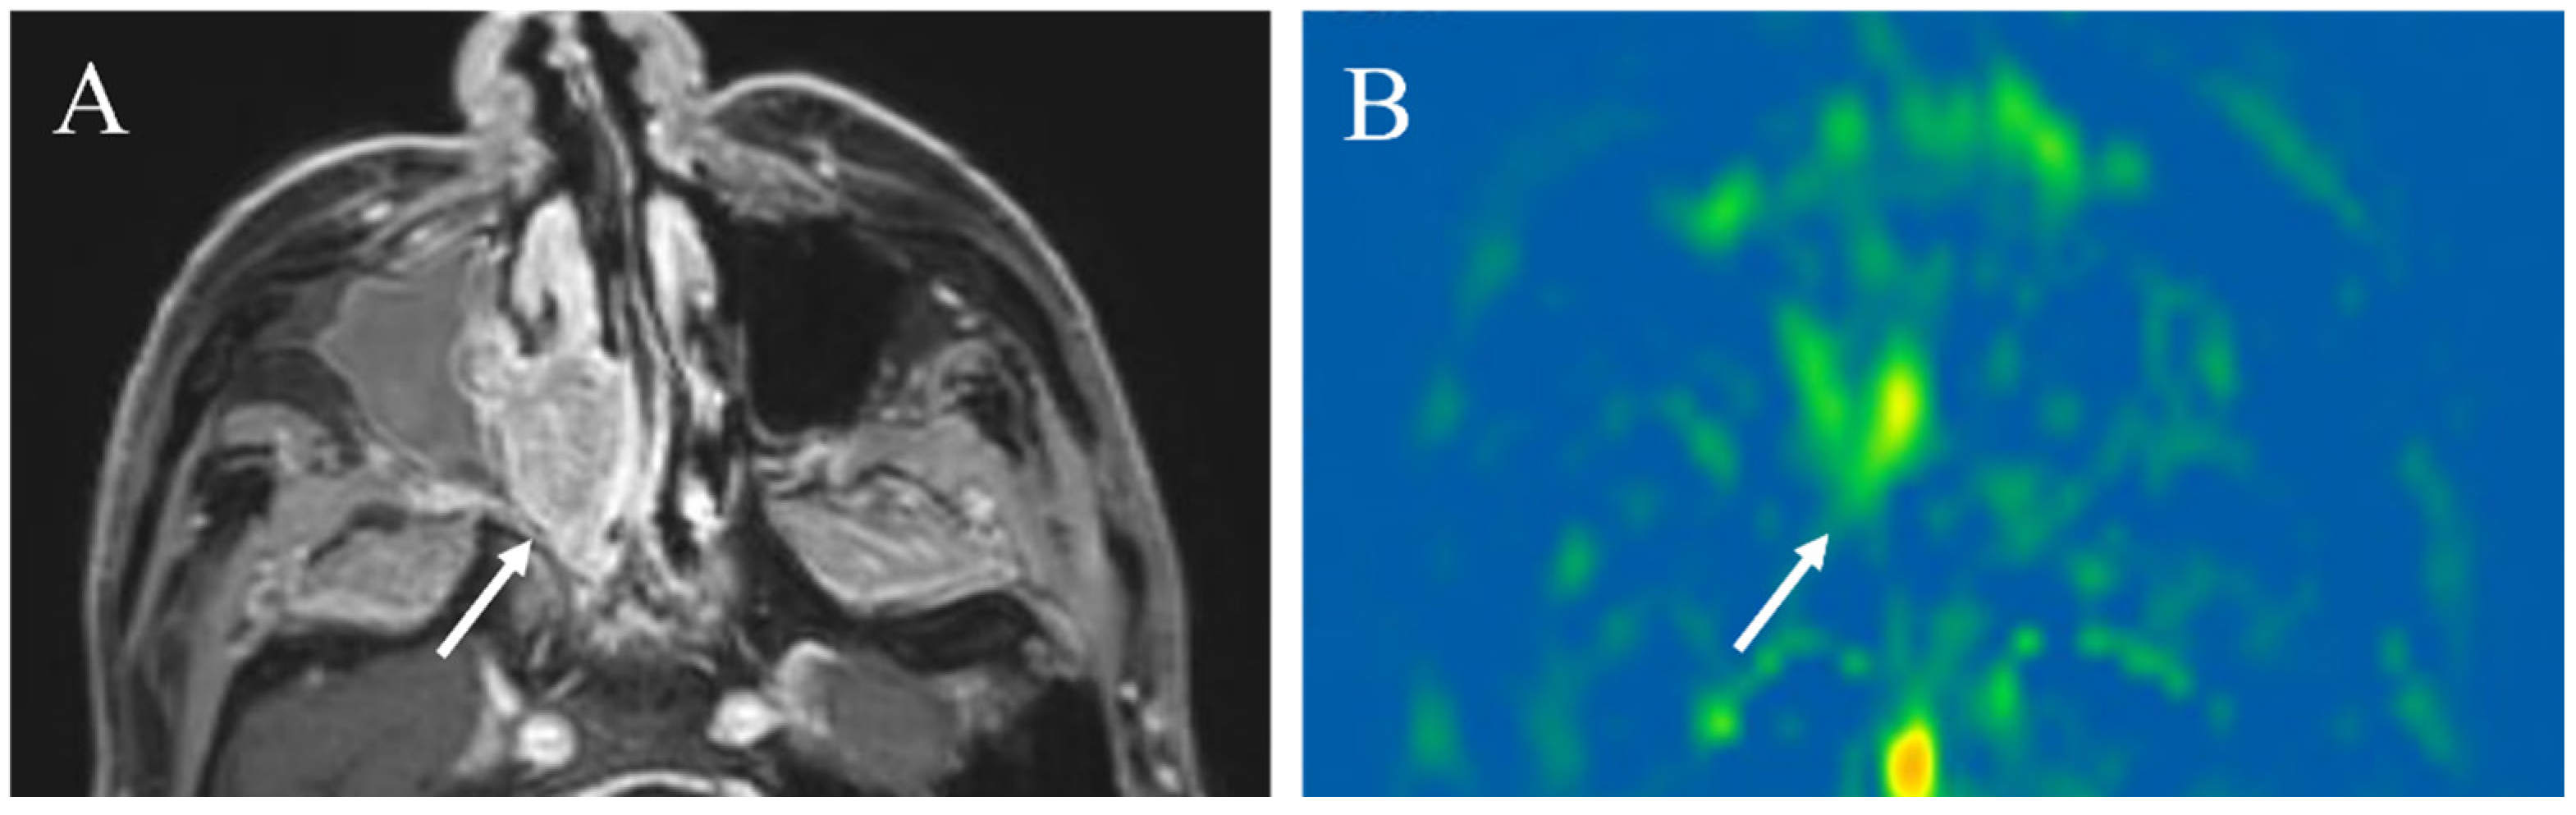

5.1.2. Hypervascular Lesions

5.1.3. Salivary Gland Tumor Differentiation: Malignant Salivary Tumors, Pleomorphic Adenomas, and Warthin’s Tumors